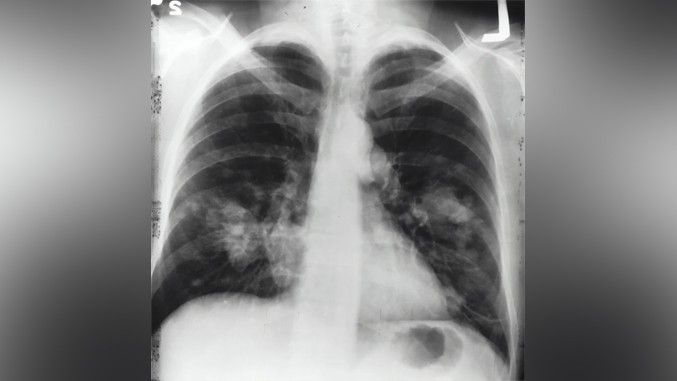

Фото: Unsplash/National Cancer Institute

Од карцинома плућа годишње у Србији оболи више од 6.000, а умре 4.600 особа. У просеку, код 16 особа дневно дијагностикује се ова врста рака, док нажалост свакодневно 13 наших грађана изгуби битку с овом тешком болешћу. Податак који додатно забрињава јесте да је у Србији током 2020. број новодијагностикованих пацијената од карцинома плућа био мањи за 25 одсто у односу на 2019. годину. То значи да код више од 1.000 људи није откривен рак због пандемије. Где су ти људи? Нажалост, не можемо рећи да је рак плућа нестао, већ да се, због отежане дијагностике, ограниченог приступа здравственим установама, али и страха људи да иду код лекара, број новооткривених случајева смањио. Због тога, према речима лекара, сада пацијенти долазе у врло тешким и поодмаклим стањима када су шансе за излечење врло мале и поред нових терапија које финансира држава. И зато је Удружење за борбу против рака плућа покренула кампању „Са њим нема дистанце” како би охрабрило грађане да не занемарују симптоме и иду код лекара.